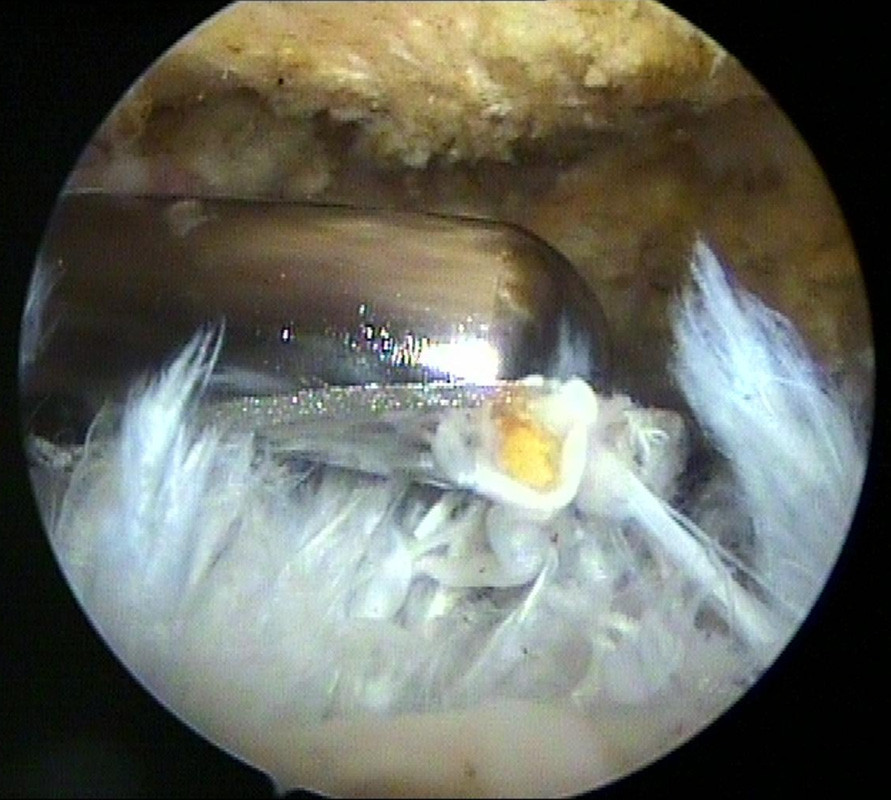

Das linke Bild zeigt den „Shaver“ beim Antragen des Knochensporns. Auf dem rechten Bild ist der Knochensporn nun abgetragen, die Sehnenoberfläche geglättet. Der Raum unter dem Schulterdach ist wieder weit genug)